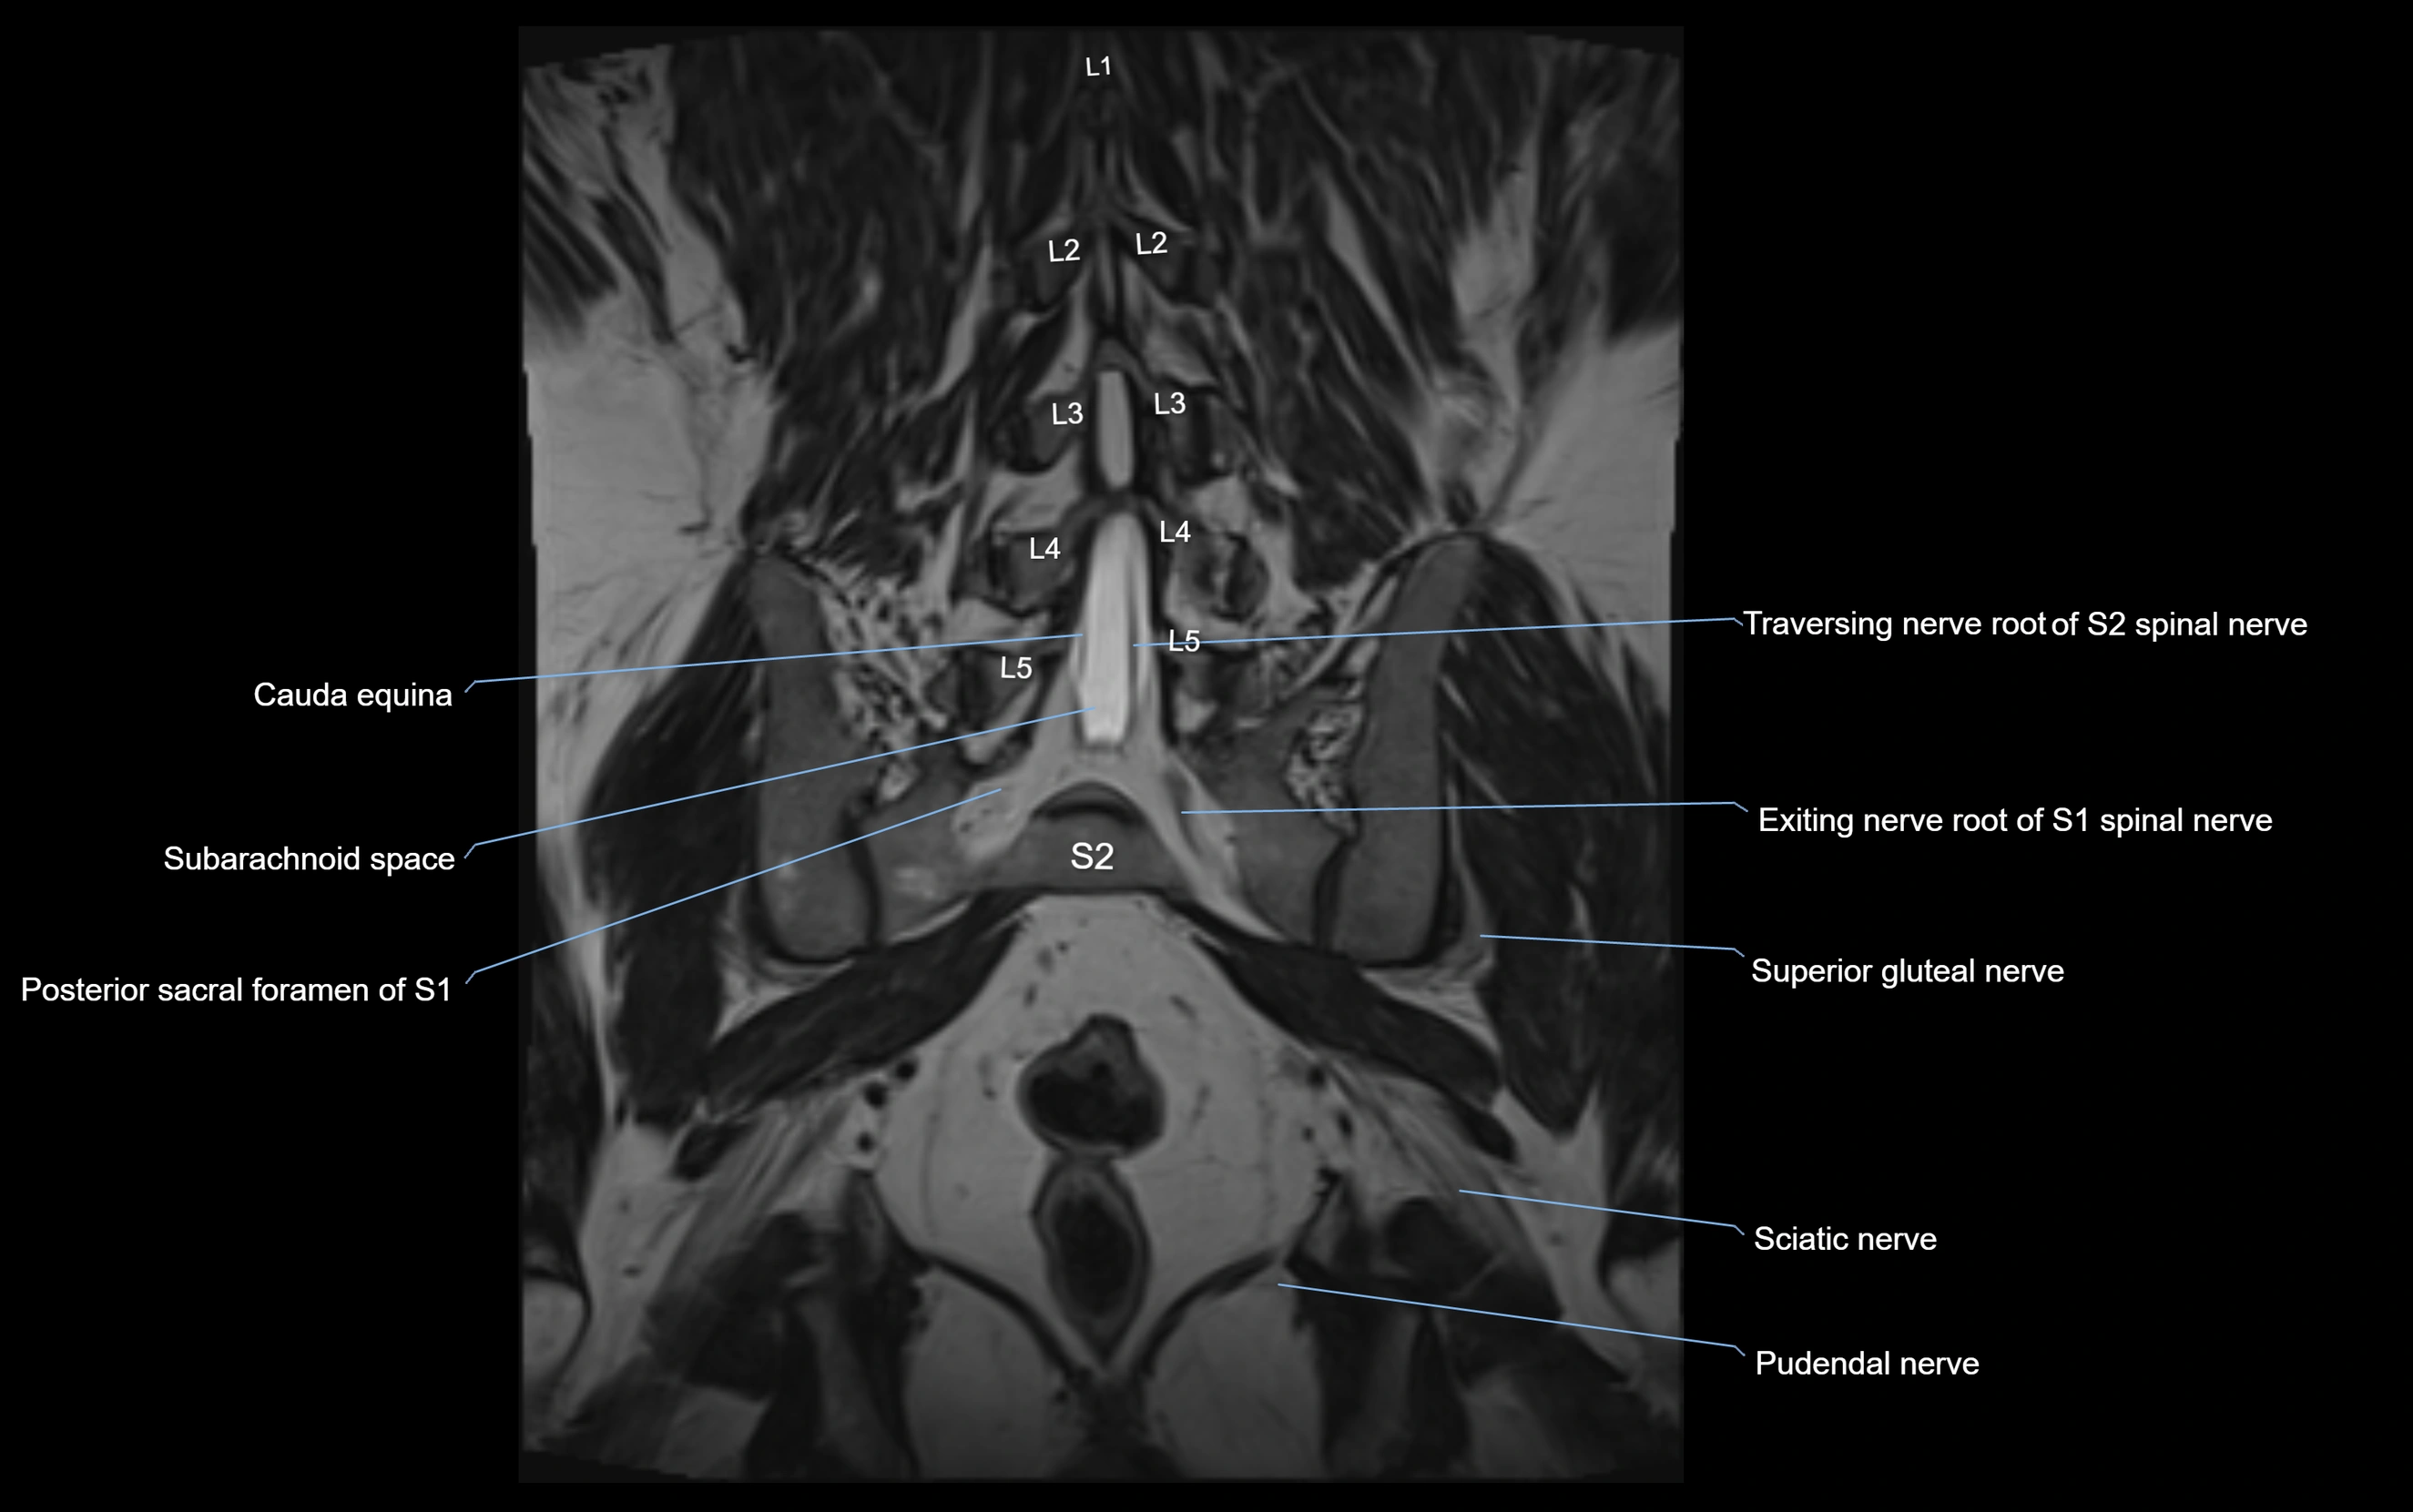

MRI image

image